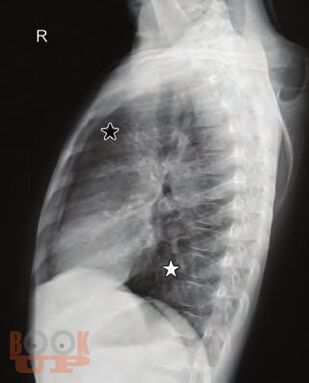

Covering various aspects of respiratory diseases in children. Multiauthored book, extensively updated by experts. Provides the key details of anatomy and applied physiology. The section on investigations has been expanded to include advanced lab investigations, pulmonary functions, and molecular tests. Common as well as rare infections, include COVID-19 infection have been covered in the section on respiratory infections. The section on noninfectious diseases covers various aspects of asthma, sarcoidosis, eosinophilic lung diseases, hydrocarbon aspirations, central hypoventilation, pulmonary hemorrhage, etc. The emerging illnesses such as primary ciliary dyskinesia, cystic fibrosis, interstitial lung diseases, etc. described in detail. These will be useful for India and other resource-limited countries. The section on acute pulmonary care including acute lung injury, mechanical ventilation monitoring and airway clearance technique that may be of immense help to practicing pediatricians who provide care for pediatric respiratory illnesses. Surgical issues that are essential for pediatricians including foreign body aspirations, intrathoracic tumors and malformations have been included. There are chapters on genetics of lung diseases, sudden infant deaths syndrome, drug and environmental diseases of lung.